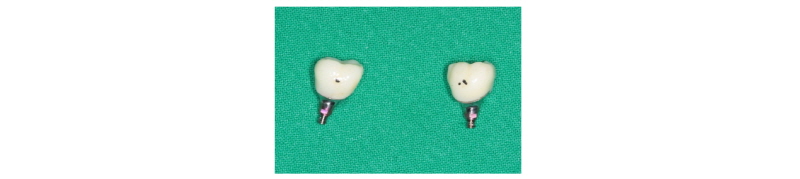

Fig. 28. Customized Titanium abutments and provisional bridge for #i36, i37. |

Ju Whan Lee : Computer-guided Flapless Implant Surgery and Immediate Loading with Customized Restoration, Comparing and Reviewing Error of Guided Surgery. Implantology 2017 |

Fig. 30. PFM bridge (final prosthesis) was cemented on #i36, i37. |

두 명의 환자 증례에서 컴퓨터를 이용한 flapless guided surgery를 시술하였고, 보철은 customized abutment와 provisional bridge를 통해 immediate loading을 하였다. 이후에 최종 수복물로 도재금관 수복하였다. 성별이 같고 연령도 비슷하였으며, 특이할 만한 전신질환은 없었다. 공통적인 시술 부위는 모두 하악 좌측 구치부였고 임플란트 수술 당시에 나타난 골질은 모두 D2였다. 각 증례에 사용한 임플란트 회사는 상이했지만, 모두 Grade IV의 SLA surface를 가진 tapered 형태의 implant fixture (Case 1: UF-II, DIO Implant, Case 2: Anyone®, Megagen)를 식립하였다. Case 1은 직경 4.0 mm, 길이 10 mm이고 internal connection type의 fixture를 2개, Case 2도 마찬가지로 internal connection type의 fixture이었는데, 직경 4.5 mm, 길이 8.5 mm 1개와 직경 4.5 mm, 길이 10 mm 1개 식립하였다. 식립 토크는 모두 35 Ncm 이상이었고, ISQ 값은 80 이상으로 측정되었다. 부위, 골질, 초기고정 등을 바탕으로 2013 ITI consensus 기준의 immediate loading하기 위한 조건에 부합하다고 판단하였다6 (Table 1, 2). 이에 Grade IV titanium block을 milling하여 제작한 customized abutment를 체결한 후, PMMA block milling한 provisional bridge를 임시 합착하였다. 4개월간의 정밀한 관찰 후, osseointegration이 성공적으로 이루어져 최종 인상 채득하여 도재 금관 수복을 하였다. 최종 인상 채득 전에 abutment screw retightening도 실시하였다. Cementation type 보철물을 제작하여 centric stop은 형성하였으나, eccentric movement에서는 간섭 없게 교합조정하였다. 2주간의 경과 관찰동안 환자의 특별한 불편함이나 합병증이 없어 임시 합착 상태에서 유지하기로 하였다.